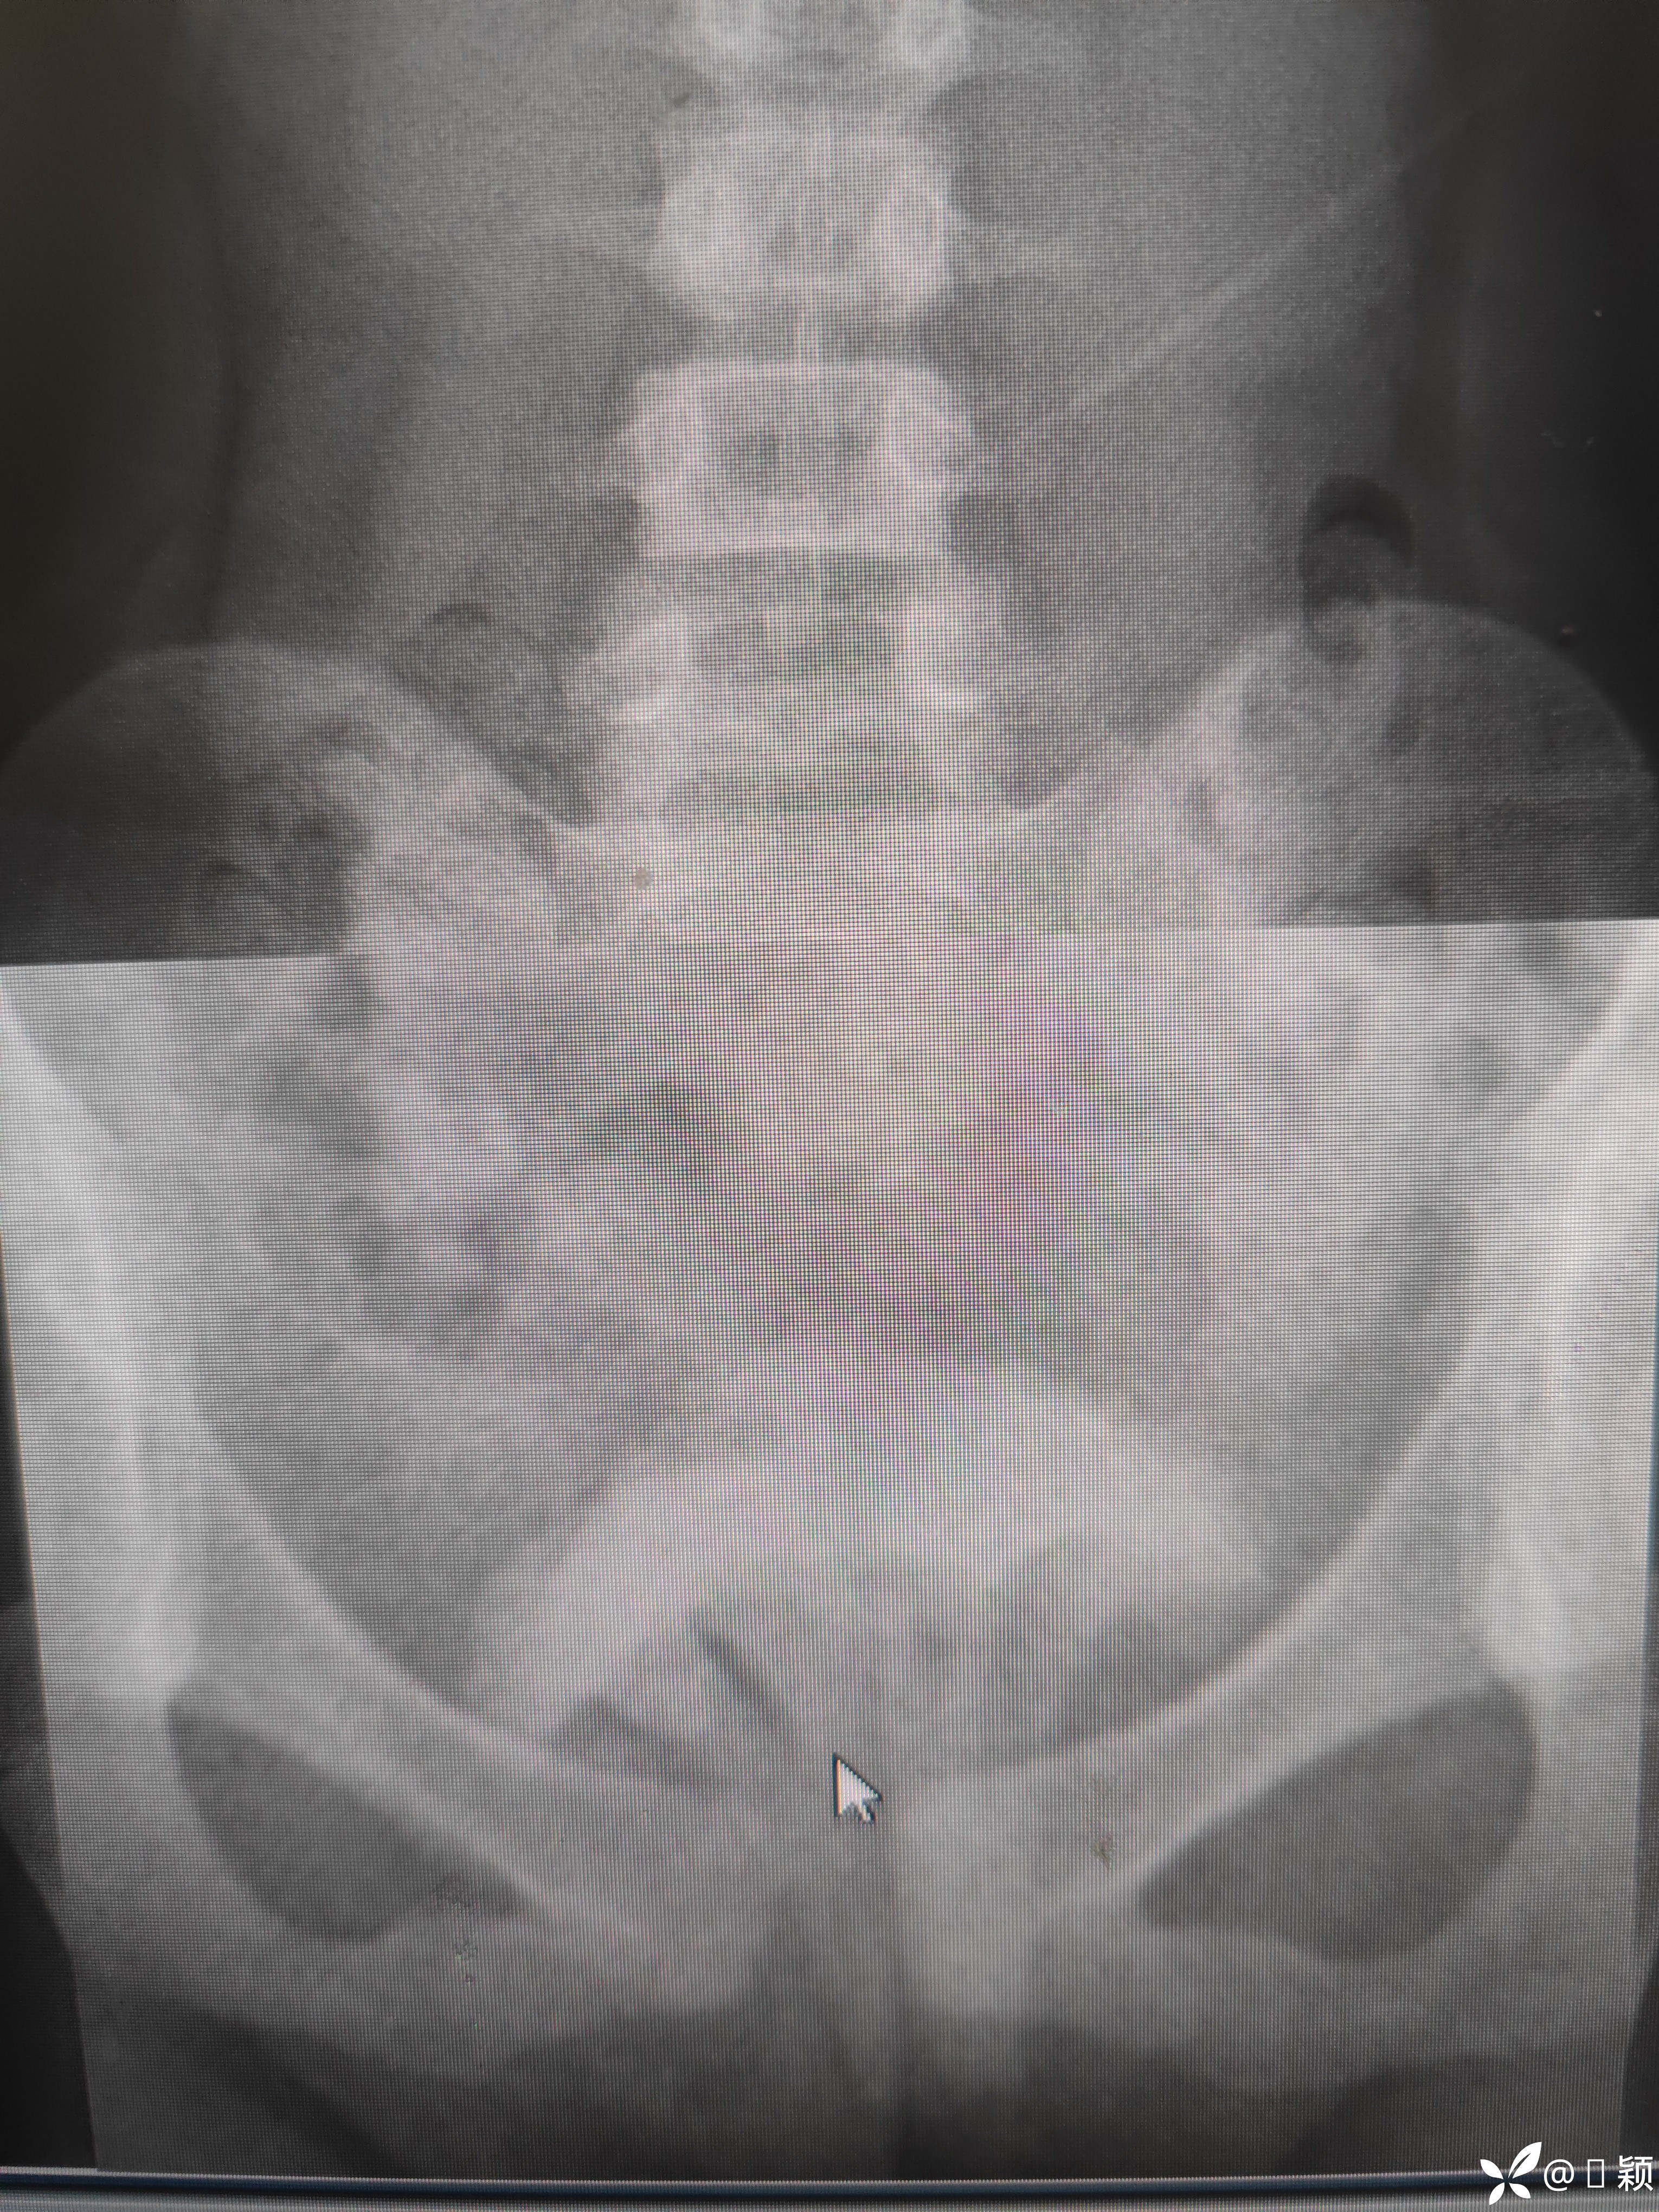

10岁女孩,留守,好奇把玩具“西兰花”塞进阴道,外阴未见损伤和血迹

请问各位同道、专家如何减少创伤把异物取出?